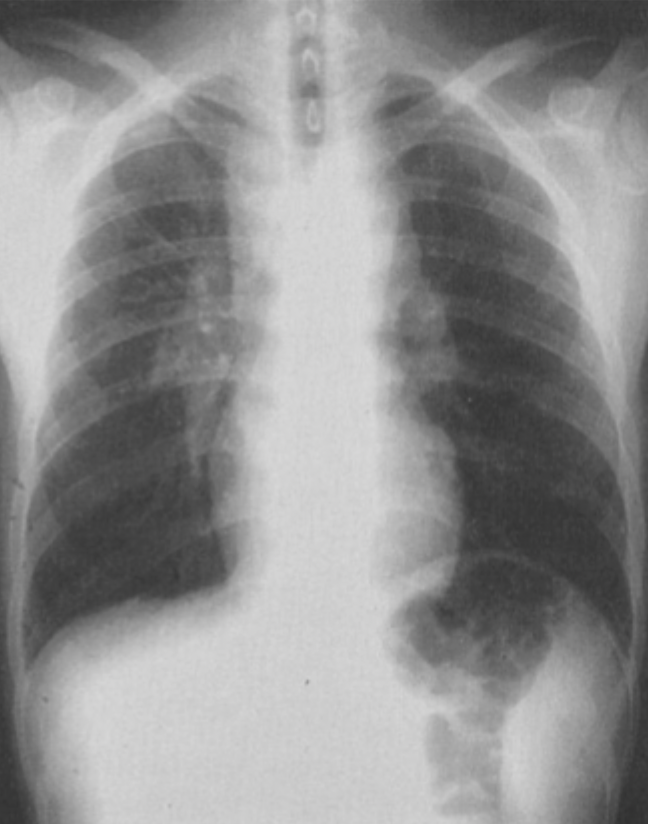

Q

What is this ?

A

Bilateral hilar lymphadenopathy